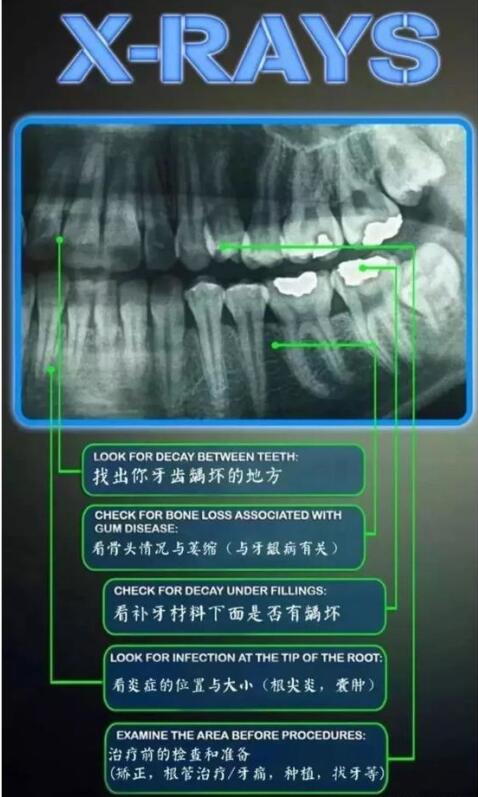

表示,补牙是相对于牙齿缺损而言的,一般造成牙齿缺损的情况是蛀牙,因为蛀牙在没有得到及时治疗的情况下,会导致牙齿的坏死和脱落。蛀牙也就是牙齿出现腐烂现象。补牙是处理蛀牙有效的方法。

2、患者牙齿龋病的程度、部位及病变的程度不一,造成了补牙难易的程度不同,从而在极大程度上造成了补牙费用的不同。